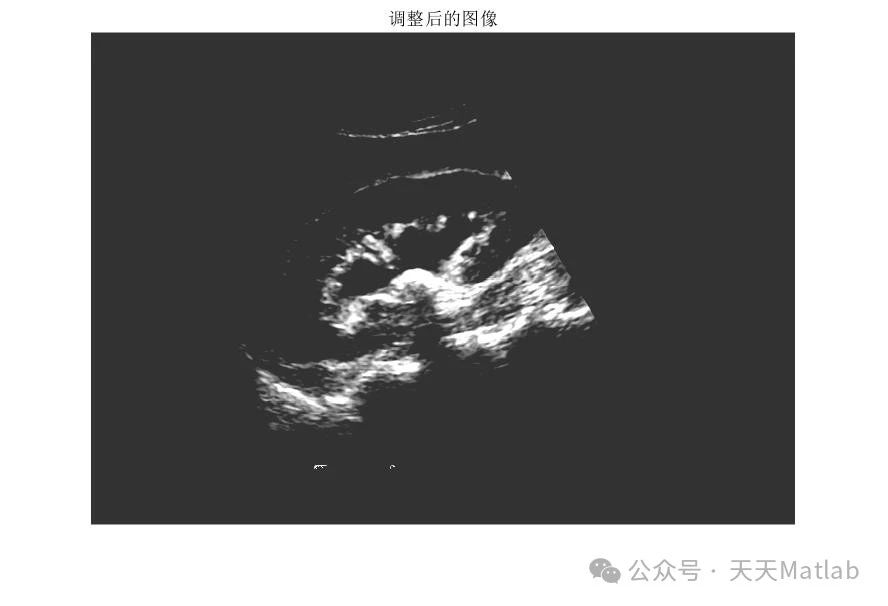

二、 肾结石识别与分割

在中值滤波去除噪声后,需要对图像进行肾结石识别和分割,以准确定位结石区域。常用的图像分割方法包括阈值分割、区域生长、边缘检测等。考虑到肾结石在X光或CT图像中通常表现为高密度区域,阈值分割法是一种相对简单且有效的方案。选择合适的阈值是关键,可以采用Otsu算法等自适应阈值分割方法,根据图像灰度分布自动确定最佳阈值,以减少人为干预。

在阈值分割后,还需要对分割结果进行后处理,例如去除小的噪声区域,填充小的孔洞,以获得更准确的结石区域轮廓。形态学操作,例如开运算和闭运算,可以有效地去除毛刺和填充孔洞。

⛳️ 运行结果